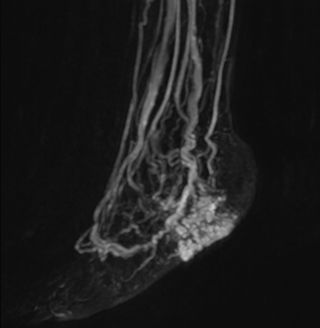

MRA of foot with 4D-TRAK XD

The images obtained with Ingenia Ambition show large coverage and high uniform signal. More vessels are visible than in a previous exam of the same patient on Achieva. The movies show a higher temporal resolution in the Ambition acquisition than in a previous Achieva 1.5T exam. Both exams use a FOV of 300 mm and voxel height and width of 0.78 mm.

Achieva 1.5T

2:30 min. TE 1 ms, TR 4 ms

Ingenia Ambition

4D Trak XD 1:54 min. TE 1ms, TR 3ms